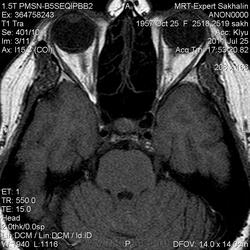

Как мы "динамичим"гипофиз

Женщина.6 лет назад выявлено образование левой доли нейрогипофиза.Пришла на контроль.

Постконтраст

Мне самой показался случай не совсем ясным, но динамик четко показывает участок с отставанием в контрастировании, воронка смещена вправо-о чем  думать бедному начинающему специалисту?